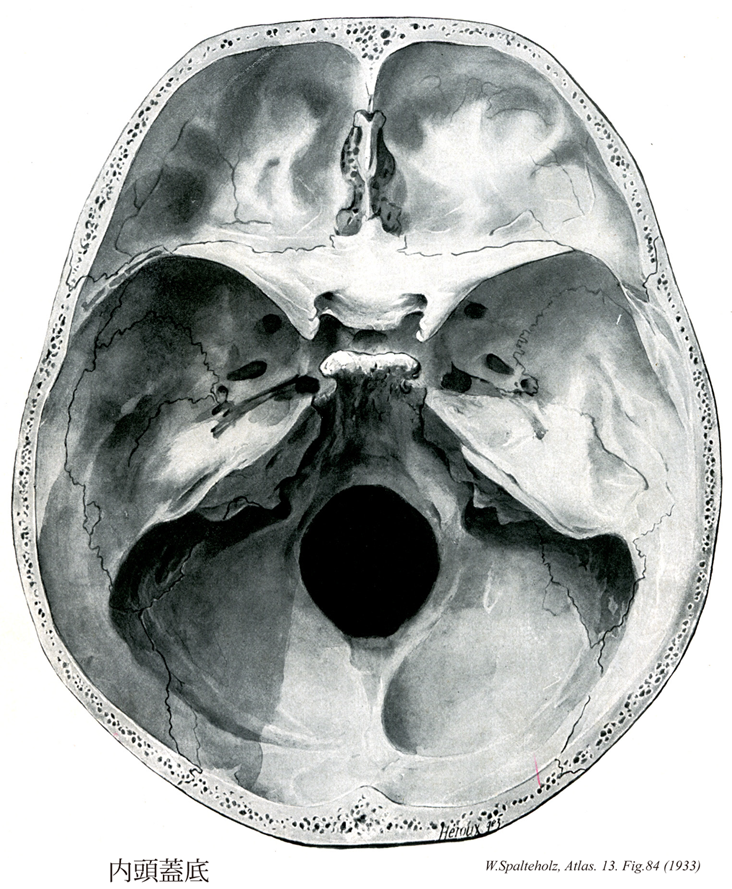

【Internal surface of cranial base

内頭蓋底;内面(頭蓋底の)

Basis cranii interna】

→(内頭蓋底は頭蓋腔の床の上面のことで、頭蓋底内面で脳をのせる深い窩をなしている。この窩はさらに前方より後方にかけて、前頭蓋窩、中頭蓋窩、後頭蓋窩の三つの窩に分けられるが、前部へいくほど階段状に高くなっている。前頭蓋窩と中頭蓋窩との境界は蝶形骨小翼および前頭骨とによってなされる。前頭蓋窩は大脳の前頭葉を、中頭蓋窩は大脳の側頭葉を、後頭蓋窩は小脳半球延髄、橋をそれぞえいれる。後頭蓋窩の前中央部には蝶形骨鞍背後面より大後頭孔までつづく斜台がある。頭蓋底内面には蝶形骨小翼を除くほぼ全域にわたって、指圧痕、脳隆起、動脈孔、静脈溝などが認められるが、これらはそれぞれ大脳の脳回、脳溝、動脈、静脈に対応して形成されたものである。)